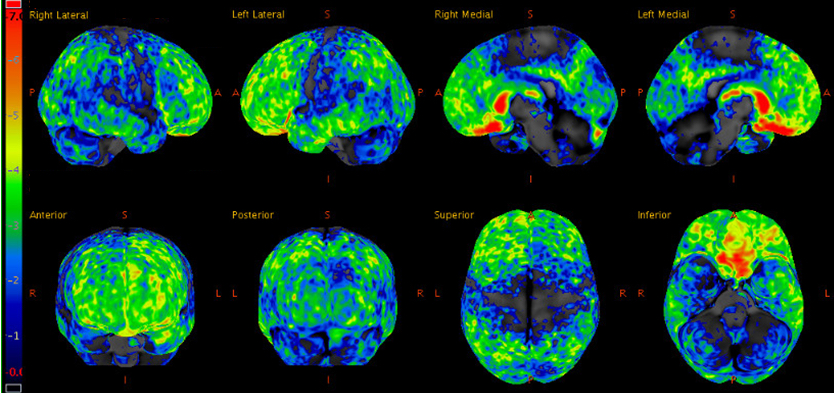

Fig2_FDG-PET_bvFTD.jpg